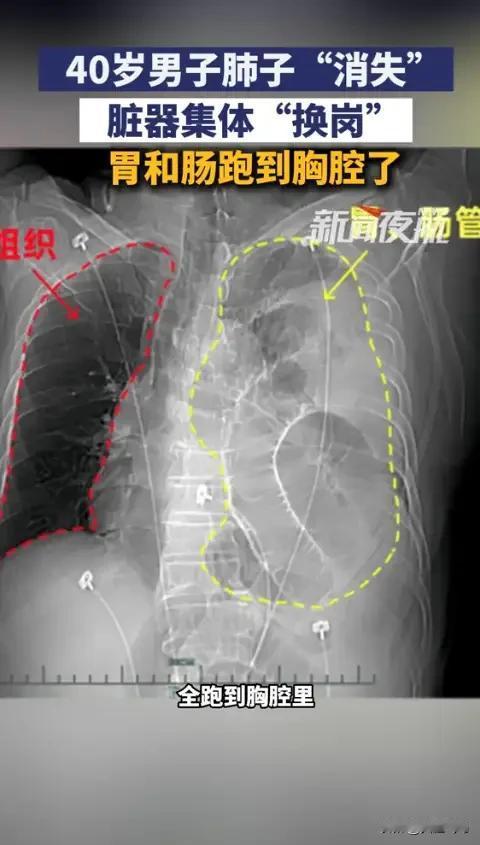

“这就是命!”浙江一男子参加活动抽奖,意外中奖获得了一次免费体检的资格。谁曾想,这场看似普通的体检,却成为他生命的转折点。体检报告出来的那一刻,医生的脸色变了——左肺竟然“消失”了!这让他和家人都惊呆了,仿佛一场噩梦突然变成了现实。 更令人震惊的是,经过详细检查,医生揭示了真相:左肺实际上被胃和肠管的移位压缩了。这不是普通的“肺不见了”,而是一场潜藏在身体深处的危机。胃肠管的严重移位,竟然把肺“挤”得几乎没有空间呼吸。要知道,平时我们只关注表面的健康,谁会想到,一场意外的体检竟然揭示了如此隐秘的“死角”。 这次幸运的发现,救了他的命!如果没有这次免费体检,问题可能早已潜藏多年,直到某天突发危机,后果不堪设想。有人说,这比中五百万还要值——因为它带来了生命的希望和第二次呼吸的可能。 这件事折射出一个深刻的社会现象:我们对健康的忽视,常常让潜在的危机变得无法预料。很多人习惯性地觉得“我还年轻”,或者“身体还行”,就放松了警惕。殊不知,疾病从不挑时间、挑年龄,它潜伏在每个人的身体深处,等待一个“机会”出现。 更令人感慨的是,现代生活节奏快、压力大,很多人忽略了定期体检的重要性。一次偶然的免费体检,成了他生命的“救命稻草”。这让我想起无数人,可能每天都在忽视身体的微妙变化,只因“没事”而忽略了健康的警钟。 或许,我们都应该像他一样,给自己多一点关爱和关注。健康不是一朝一夕的事情,而是点点滴滴的积累。每一次体检、每一次身体的自我感知,都是对生命的尊重和呵护。毕竟,生命只有一次,没有重来。 这件事告诉我们:命运或许充满变数,但我们可以用行动去掌控。别等到“命”已经到来时,才惊觉健康的重要。主动体检、关注身体的每一个信号,也许就能在关键时刻,迎来一场生命的奇迹。 所以,下次体检,不要犹豫。也许,你的“幸运”就在下一次等待你揭晓的那一刻。生命的奇迹,可能就在你我身边,只差一点点的关注和坚持。